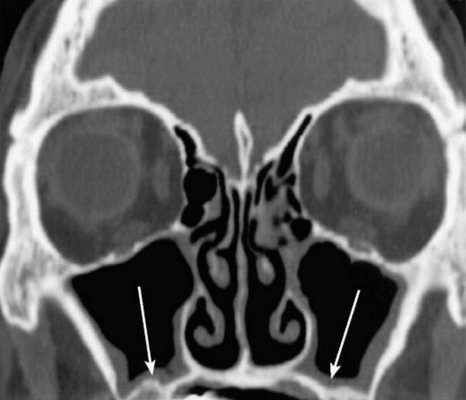

КТ.Увеличенный этмоидальный пузырь (стрелки).